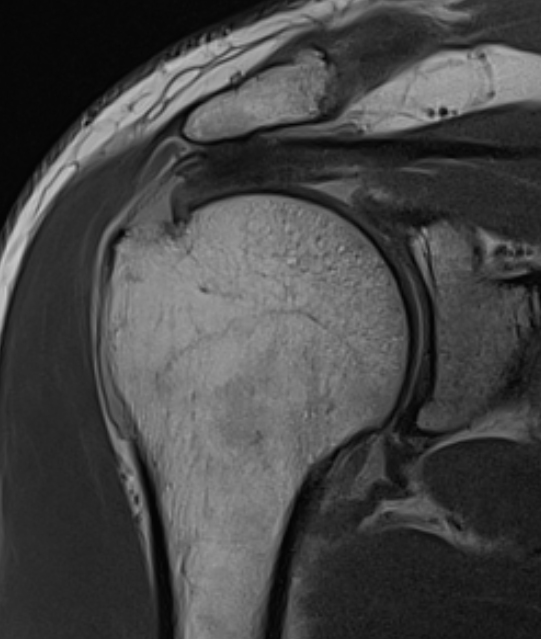

MRI

Look for

- supraspinatus / infraspinatus / subscapularis / long head of biceps pathology

- partial verus full thickness

- size of tear in coronal and sagittal planes

- retraction

- atrophy / fatty infiltration

Goutallier classification

Amount of fatty degeneration in rotator cuff muscle belly on a T1 sagittal MRI

- systematic review of Goutallier grade and retear rates

- retear rates after surgical repair increase as the Goutallier stage increases

Stage 0: normal muscle

| Stage 1 | Stage 2 |

|---|---|

|

Some fatty streaks MRI shows some fatty streaks in supraspinatus |

More muscle than fat MRI shows grade 2 in supraspinatus |

|

|

| Stage 3 | Stage 4 |

|---|---|

|

Equal fat and muscle MRI demonstrates grade 3 supraspinatus and infraspinatus |

More fat than muscle MRI demonstrates grade 4 infraspinatus |

|

Supraspinatus atrophy

Tangent sign

- sagittal MRI

- line connecting superior coracoid and superior border scapular spine

- if supraspinatus muscle is below line, there is significant atrophy

- positive tangent sign / significant atrophy associated with larger tears / irrepairable tears

Negative tangent / no atrophy Positive tangent / significant supraspinatus atrophy